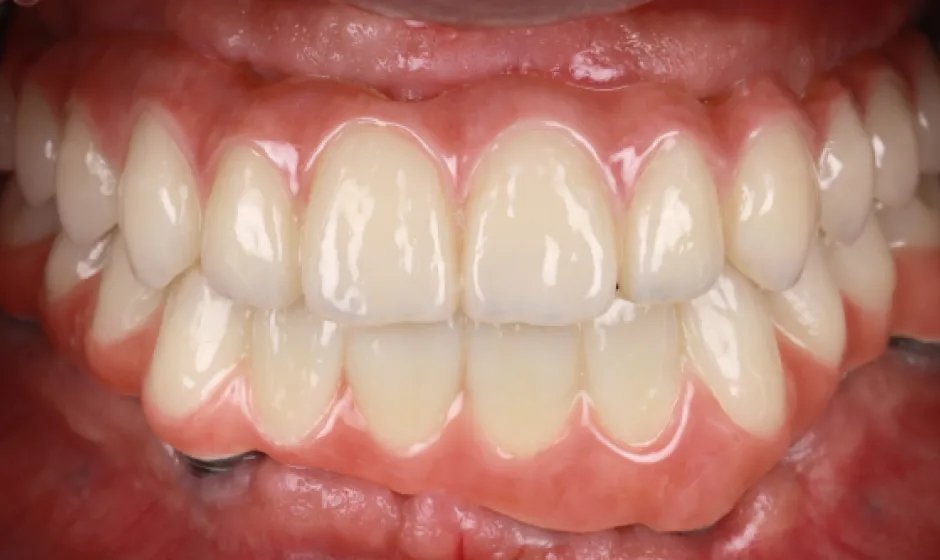

03歯がボロボロの方への

全顎治療むし歯や歯周病が広がり、「どこから治せばいいのか分からない」状態は、痛みだけでなく食事や会話、見た目のストレスにもつながります。医療法人大杉歯科医院では、まず精密に検査し、残せる歯・治療が必要な歯を見極めたうえで、治療の優先順位を整理します。仮歯で噛み合わせを整えながら、補綴やインプラントなどの選択肢を組み合わせ、機能と審美の両立を目指します。

いきなり理想を押しつけるのではなく、現実的に続けられる計画で、お口全体を立て直す治療をご提案します。症例1